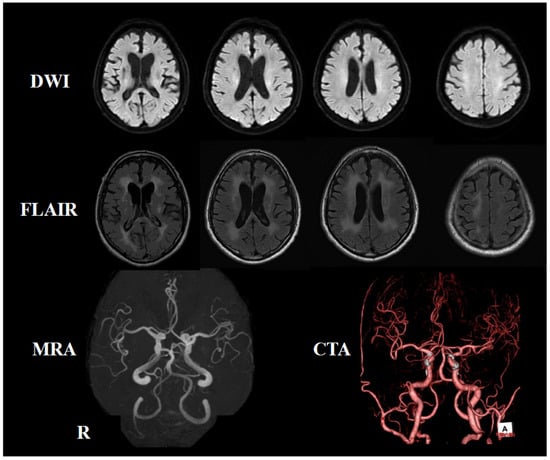

2. Case Presentation